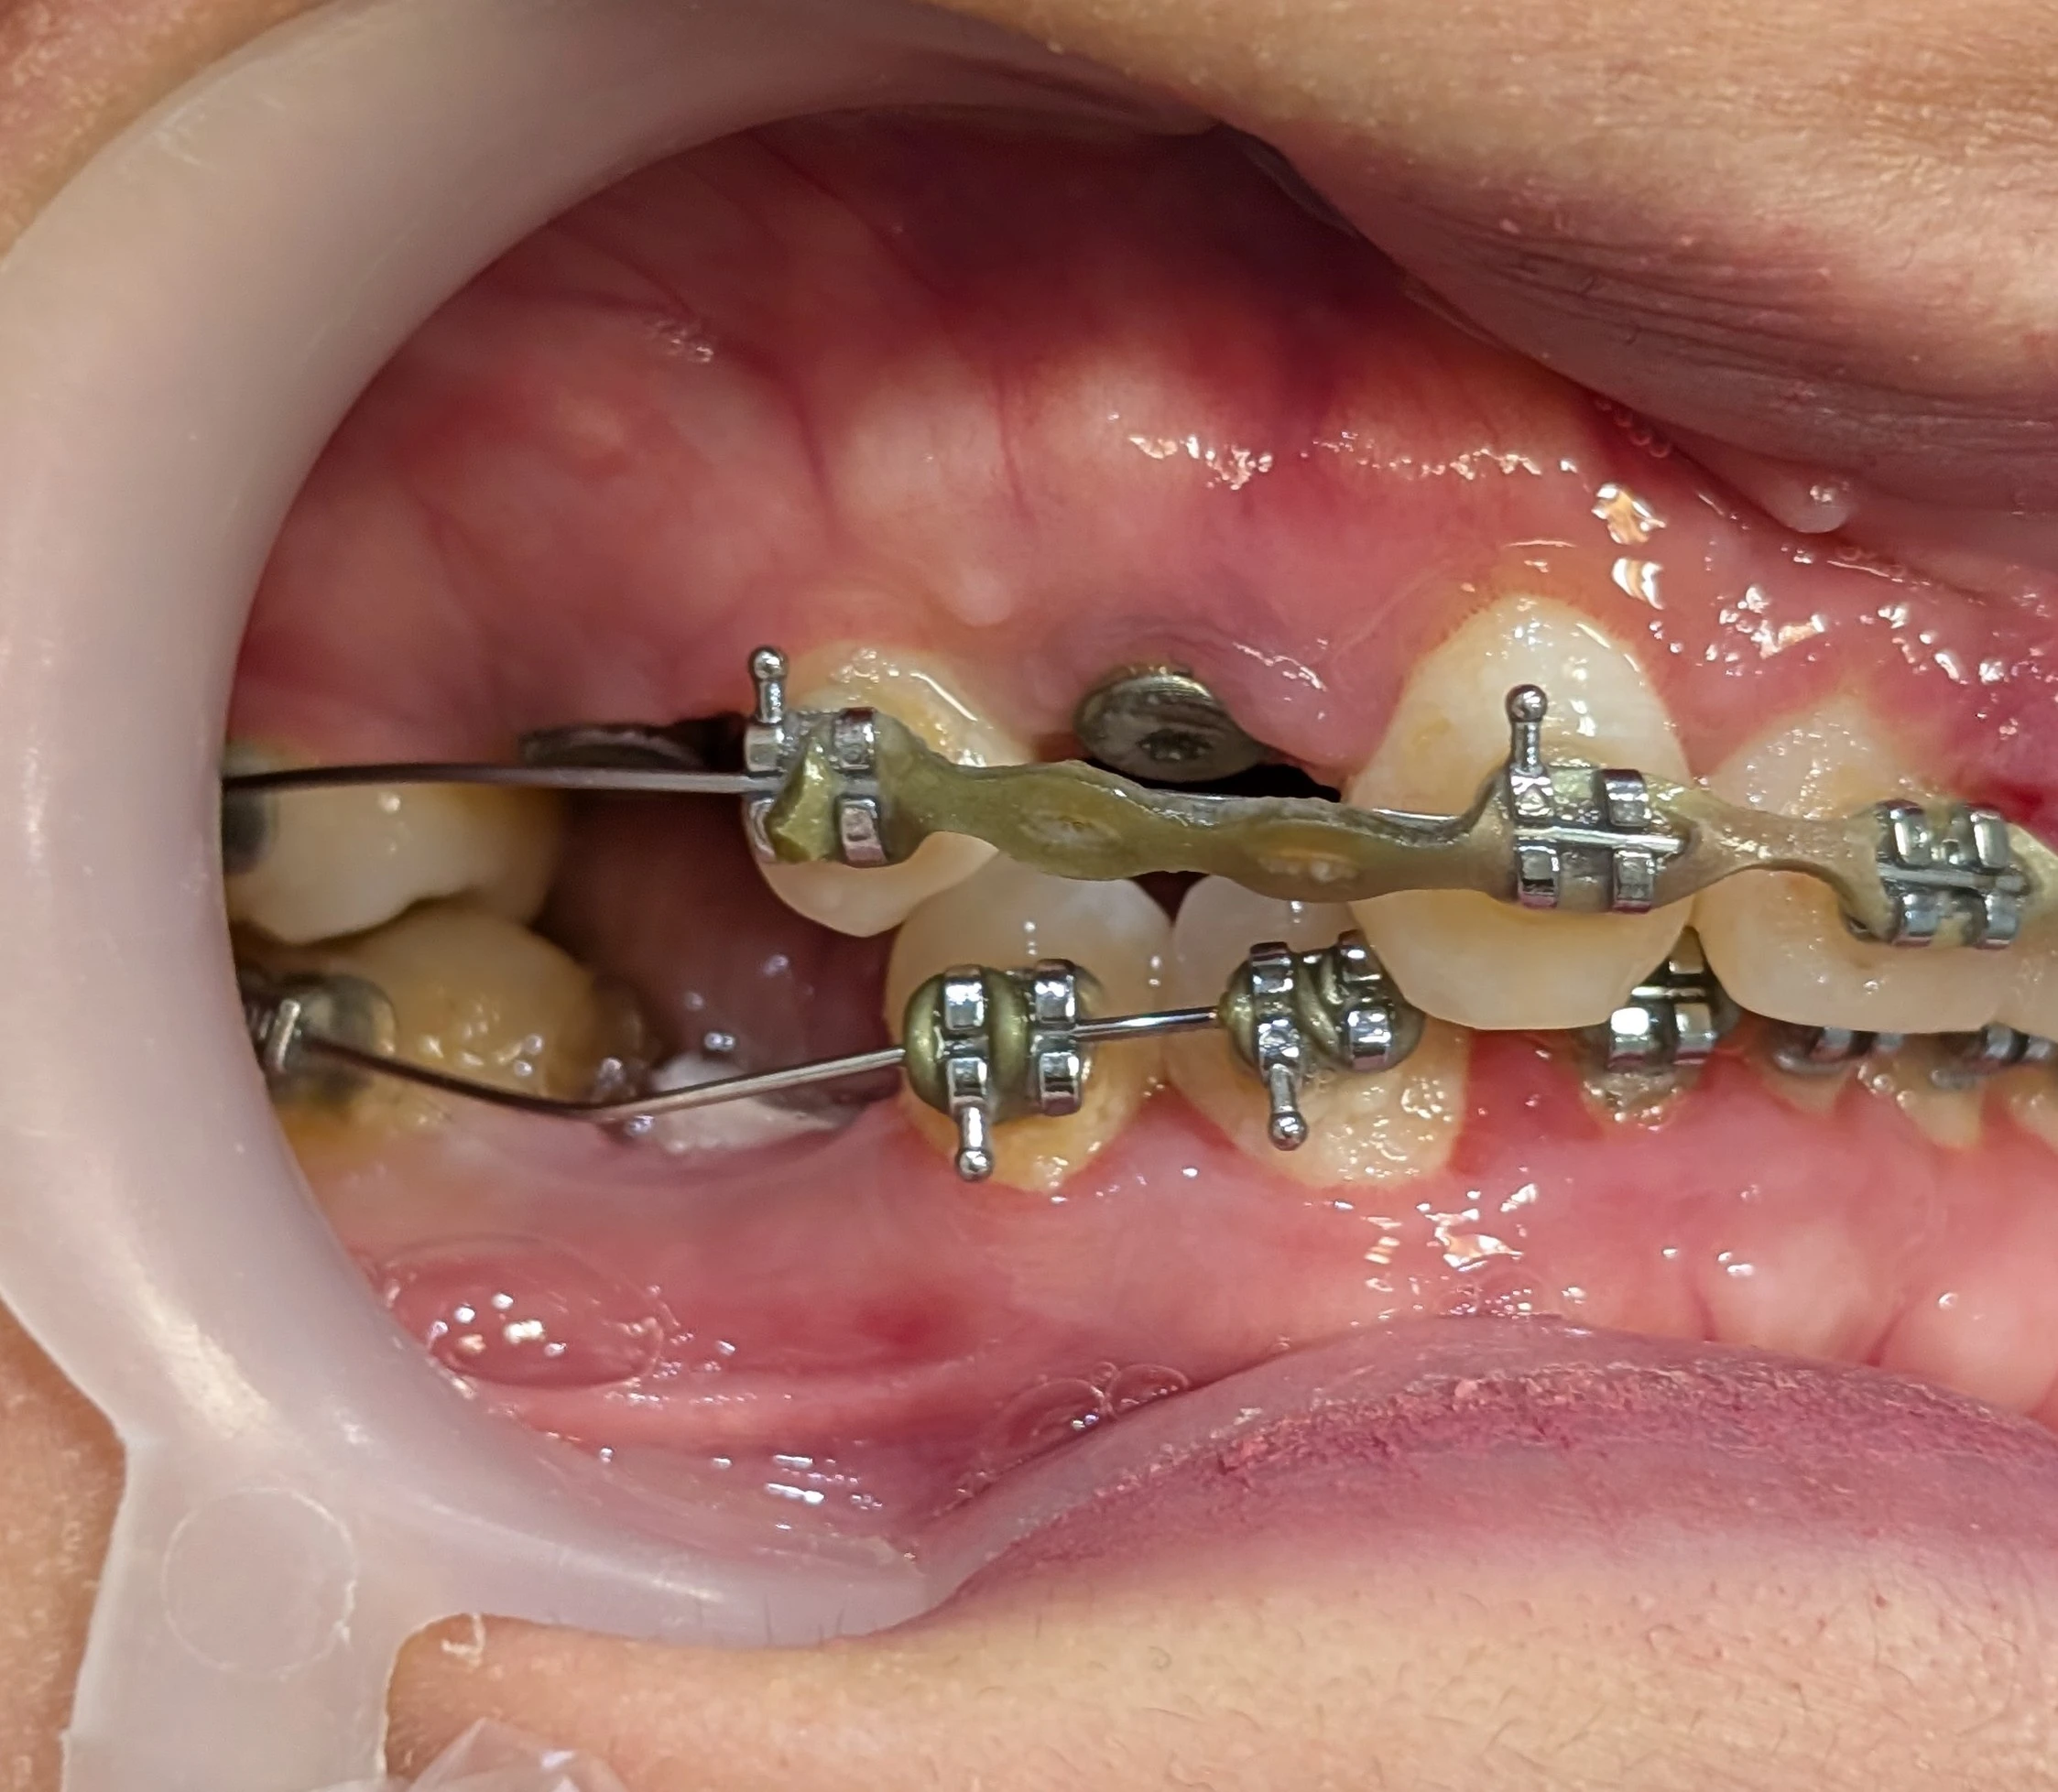

Space analysis for premolars

امروز بیماری از طرف متخصص ارتودنسی برای ارزیابی فضا ارجاع شد. سؤال ساده بود: «فضاها مناسب‌اند یا نه؟»

پشت کانین، فضایی وجود داشت که برای یک پرمولر واضحاً زیاد بود؛ آن‌قدر زیاد که اگر بخواهیم استاندارد آناتومیک را رعایت کنیم، عملاً به ساخت یک مولر در موقعیت پرمولر می‌رسیم.

و اینجاست که مسئله فقط میلی‌متر نیست. نمای مولر بلافاصله پشت کانین برای اکثر بیماران خوشایند نیست. از نظر بصری سنگین است.

به همین دلیل حتی ساخت موقت هم انجام نشد. فضا در همین مرحله رد شد و نامه برای ارتودنتیست ارسال گردید.